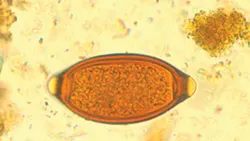

2. How are T vulpis and its eggs identified?

T vulpis eggs (See Figure 1) are most commonly identified on fecal flotation. Direct saline smear examination is insensitive, with one study showing 92.7% false-negative results when comparing direct smears to fecal centrifugation.1 T vulpis eggs are barrel or football shaped and yellow-brown with prominent bipolar plugs. Trichuris ova are smooth shelled and measure ~79 x 38 µm.

Figure 1

T vulpis eggs are yellow–brown and barrel or football shaped with prominent bipolar plugs.